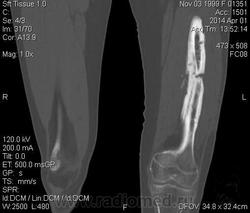

Молодая дама (14 лет) с переломом срдней трети диафиза левого бедра в анамнезе (декабрь 2012 г). Ломала ногу несколько раз в этом месте. Сейчас состояние после МОС. Как следует понимать изменения в кости, формируется ли ложный сустав?

Похоже ложный сустав сформировался. Но при нём обычно большие напластования костной мозоли, здесь их нет. В таких случаях смотрю при скопии подвижность.

Ох, не хочется думать о ложном суставе в 14 лет... По срокам под ложный сустав подходит, он характеризуется замыканием костномозгового канала с формированием подобий суставных поверхностей. У нее же есть хиленькая периостальная костная мозоль по задней поверхности бедра удерживающая отломки в правильном положении. Я склонна думать, что это скорее застарелый перелом (оно же замедленная консолидация). Здесь очень важно посмотреть предыдущие снимки (поиск рефрактуры, либо отсутствия полной консолидации).

Настоящего, родного ложного сустава пока нет, хотя костномозговой канал дистального отломка уже закрыт - образовалась склерозированная замыкательная пластина. Варусная деформация почти в 165 градусов... Я бы заключилась неполной консолидацией и варусной деформацией, прогностически формирование ложного сустава очень вероятно.